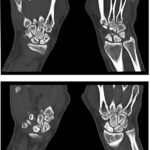

CT Right Scaphoid Scan

Medifyhome offers the right view of the scaphoid bone in the wrist through the CT Right Scaphoid image. A fast and very safe CT scan of the bone is taken to confirm fractures, bone or joint damage that may not have shown up on an X-ray. Advanced scans, such as the CT Right Scaphoid Scan, provide a clear picture of cross-sections from all angles to doctors so that they can analyze any harm and any abnormalities in detail. Professionalism makes Medifyhome’s way comfortable, and our scanning equipment brings prompt and accurate results. Therefore, if a detailed, careful examination of your scaphoid is required, you can easily book your CT Right Scaphoid at Medifyhome, just by dialing our customer care at +919100907036 or +919100907622.

A CT Right Scaphoid Scan is a scan that focuses on the specific bone of the wrist called the scaphoid. This technique produces cross-sectional images of the right scaphoid at a high level of anatomic detail using computed tomography (CT) imaging. The particular indication for use of CT scanning in fractures, arthrosis, and non-union of scaphoid fractures or other bone pathologies not visualized on standard x-ray establishes the non-invasive test as highly valuable for doctors who want to know more details of the exact bone structure to determine the degree of injury and give appropriate treatment. It is fast, precise, and ensures optimum insights for good care.